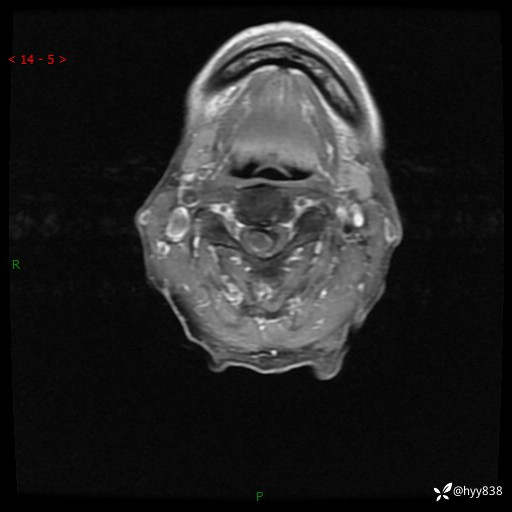

颈椎MRI平扫(sag T1WI+T2WI-fs+axi T2WI)

CE